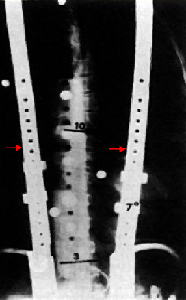

(يمين) صورة أشعة سينية X-Ray لمثصاب بالجنف صُحح بإستخدام حزام ميلواكي Milwaukee Brace (يسار)

العلاج بالعمليات الجراحية

بالنسبة للعمليات الجراحية لتصحيح الجنف Scoliosis Orthosis جميعها تعتمد على صهر (دمج) Fusion الفقرات المُصابة بالجنف مع بعضها. و هذا الصهر يمكن أن يكون أمامي Anterior Fusion أو صهر خلفي Posterior Fusion , مع استخدام أنظمة جراحية لتصحيح الجنف و هذه الأنظمة عبارة عن قضبان و براغي تُثبت بفقرات العمود الفقاري للتقليل من زاوية الإنحناء و جعل الفقرات مصطفة عمودياً قدر الإمكان. نذكر منها قضيب هارينغتون Harrington Rod و هو نظام مستخدم منذ الخمسينيات و النظام مُتعدد الخُطاف و القضبان Multiple Hook-Rod System .